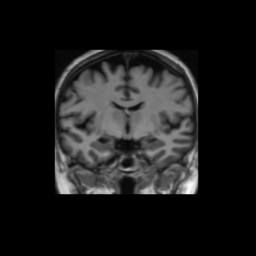

Accuracy is reported as Dice overlaps between a tool's segmentation and the Internet Brain Segmentation Repository (IBSR) manual segmentation for each of the 18 IBSR subjects. The inter-tool comparison (on the left below) shows the median Dice coefficient for each tissue class. The overlaps for FSL (from which the median values are drawn) are shown in the plot on the right.

Overlap coefficients for each tissue class are shown here for each IBSR subject. Select a subject below to see the FSL results compared to other tools.